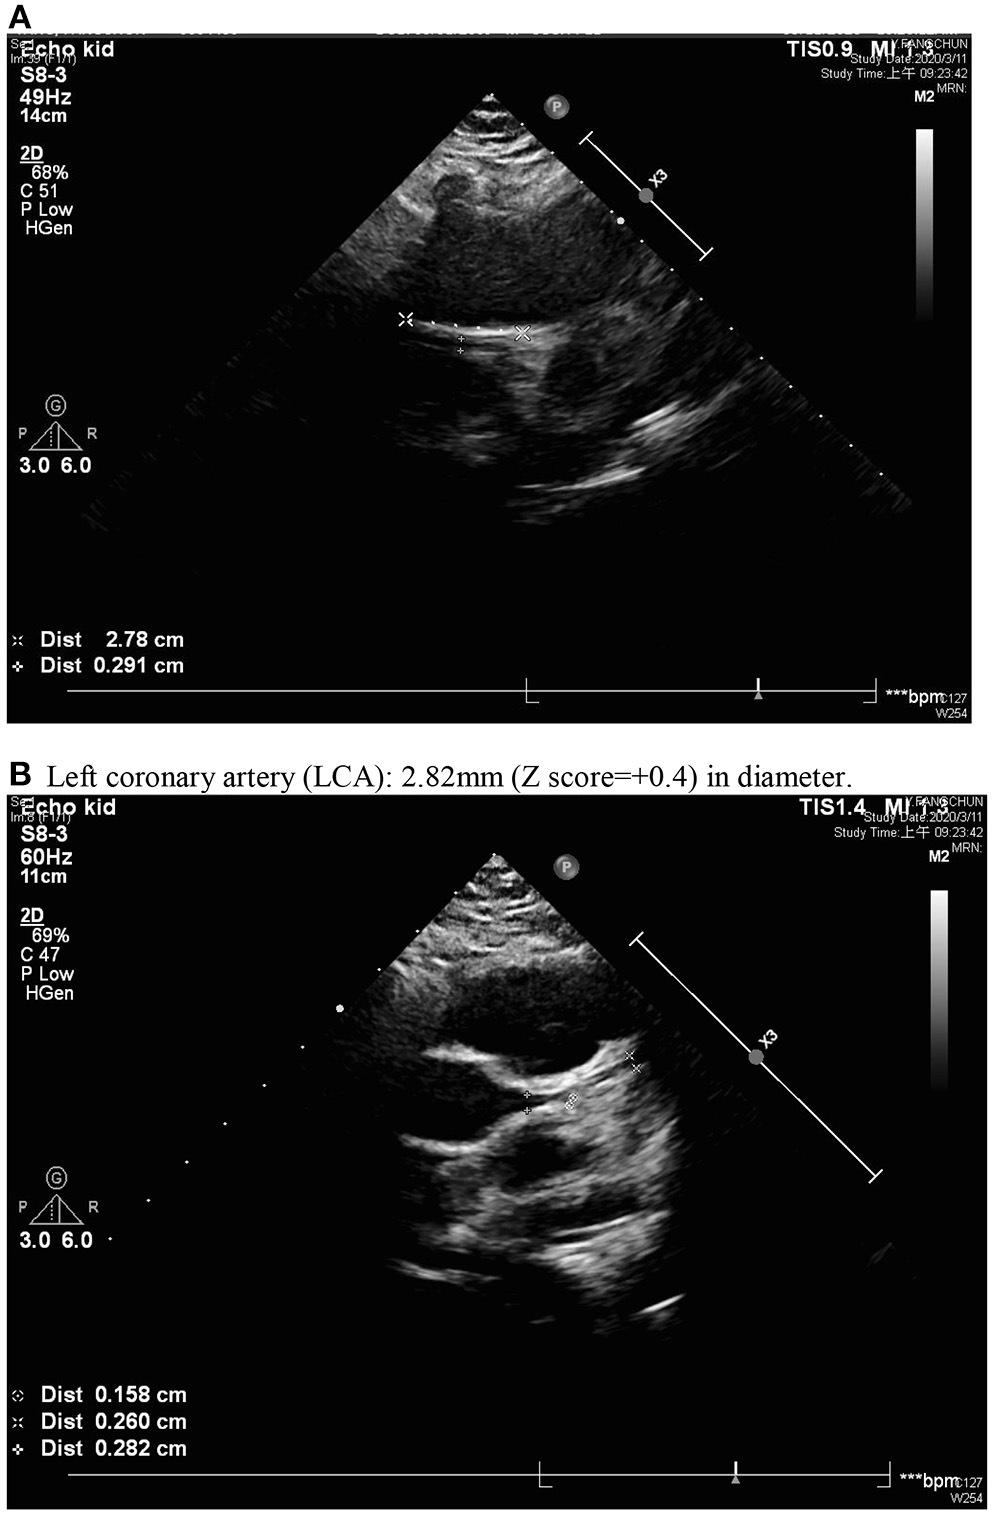

A previously healthy 10-year-old Taiwanese boy presenting with a high fever for 12 days was admitted to another hospital in year 2019. Prior to admission to our hospital, he showed bilateral conjunctival injection, erythema of the lips and neck, and lymphadenopathy. No BCG site induration was observed, nor was skin rash or limbs induration found. After the patient was admitted to our pediatric ward, the laboratory analysis revealed evidence of mild leukocytosis (10,600/μl), thrombocytosis (557,000/μl), and high C-reactive protein (CRP) (132.22 mg/L), without acute liver or kidney injury. A two-dimensional echocardiography on day 1 of admission (day 12 of illness) revealed a 4.12 mm aneurysm (BSA-adjusted Z score = 3.17) of the right coronary artery (RCA) with general dilatation of the RCA and LCA. High-dose intravenous immunoglobulin (IVIG, 2 g/kg) infusion was prescribed during admission (day 12 of illness). After being discharged, the RCA still progressed to a mid-sized aneurysm 6.08 mm (Z score: 4.85) in diameter and 35 mm in length (day 20 of illness) (Figure 1). Parents were directed to give hydrogen gas inhalation at least 1 h per day for the patient (77% hydrogen with 23% oxygen, 70~75 liter/hour) at home by themselves until aneurysm regression. The follow-up echocardiography showed regression in the aneurysm, which was then 5.37 mm in diameter and 12 mm in length of RCA (day 34 of illness) and 4.56 mm × 8.68 mm (day 48 of illness), then 4.16 mm (day 62 of illness). The mid-sized aneurysm regressed to within normal range with 2.91 mm in diameter (Z score = 1.46) on day 138 of illness (Figure 2). The following laboratory data showed normal liver enzyme (aspartate aminotransferase/ alanine aminotransferase: 24/17 U/L), renal function (blood urine nitrogen/creatinine: 18.0/0.52 mg/dl, estimated glomerular filtration rate: >60 ml/min), total white blood cell count: 11,800/ul (leukocytosis), hemoglobin: 14.2 g/dl, platelet: 258,000/ul, segment: 67%, lymphocyte: 26%, monocyte: 5%, eosinophil: 0%, basophil: 0%, sodium: 143 mEq/L, potassium: 3.7 mEq/L, chloride: 107mEq/L, albumin: 4.6 g/dl, calcium: 9.7 mg/dl, eosinophil cationic protein: <2.0 microgram/L and total immunoglobulin E: 107 KU/L. The laboratory data from acute and chronic stage (after hydrogen gas inhalation) were showed in Table 1. We reported on this case using a medical chart review retrospective, and the institutional review board (IRB) of Chang Gung Memorial Hospital approved this study (IRB No.: 201900827B0).

Figure 2

Normal inner diameter and origin of coronary arteries; regressed right coronary artery with a diameter of 2.91 mm (A) and normal left coronary artery (LCA) (B). (B) Left coronary artery (LCA): 2.82 mm (Z score = +0.4) in diameter.